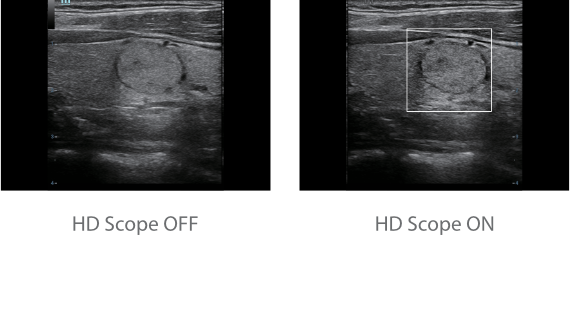

Dank der ZONE Sonography?-Technologie (ZST+) wird das B-Bild des Resona 7 ├╝ber die komplette Tiefe fokussiert, sodass keine Fokuspunkte mehr gesetzt werden m├╝ssen. Die Schall-Lauf-Geschwindigkeit (SSC) wird auf Knopfdruck individuell auf den Patienten angepasst, was die Darstellung von Organen, Grenzfl?chen und Gewebever?nderungen erheblich verbessert. Und dank der fortschrittlichen iFusion-Funktion k?nnen optional die Daten von Ultraschall-, MRT-und CT-Bildern synchronisiert werden.